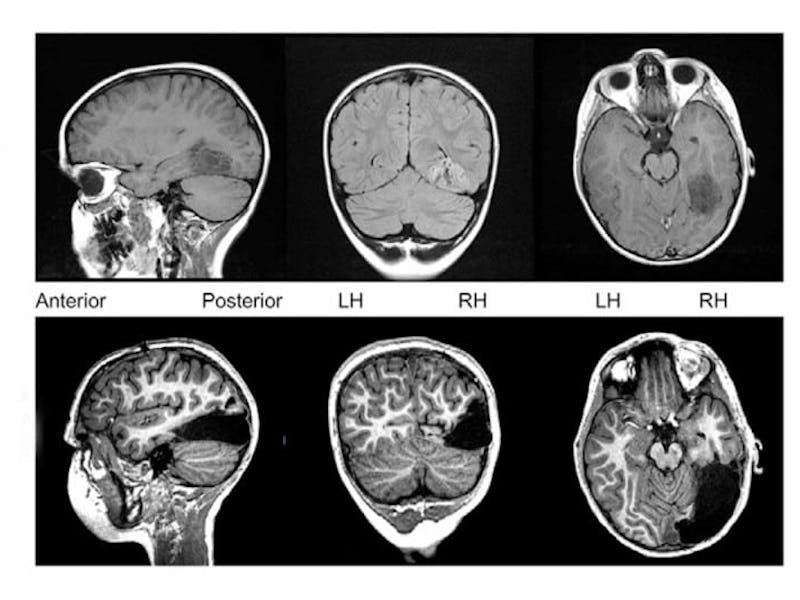

This image shows just how much of the boy's right hemisphere was removed. The black dotted lines show where there used to be brain matter.

Doctors documented the boy’s case in a paper published July 31 in the journal Cell Reports. They report that despite the boy having a significant portion of his brain removed, including the portion associated with visual processing, the boy has developed into a healthy 10-year-old. And while he still can’t see in the left side of his field of vision, his brain has reconfigured some of the lost connections so that he is able to recognize people’s faces. All in all, the doctors see it as a successful procedure, as well as evidence of the brain’s plasticity — its ability to adapt — when it comes to higher-order functions.

In the case study, doctors explain how, starting at age 4, the boy suffered from debilitating epileptic seizures. They soon discovered that the culprit was a slow-growing tumor in his occipital and temporal lobes in the right hemisphere of his brain, but he didn’t respond to any treatments to relieve him of his seizures. So nine months after his sixth birthday, doctors removed one-third of the right hemisphere of his brain, including some of his temporal lobe and his entire occipital lobe. While the occipital lobe is charged with visual processing, the temporal lobe also handles some degree of processing visual and auditory information, including, notably, facial recognition.